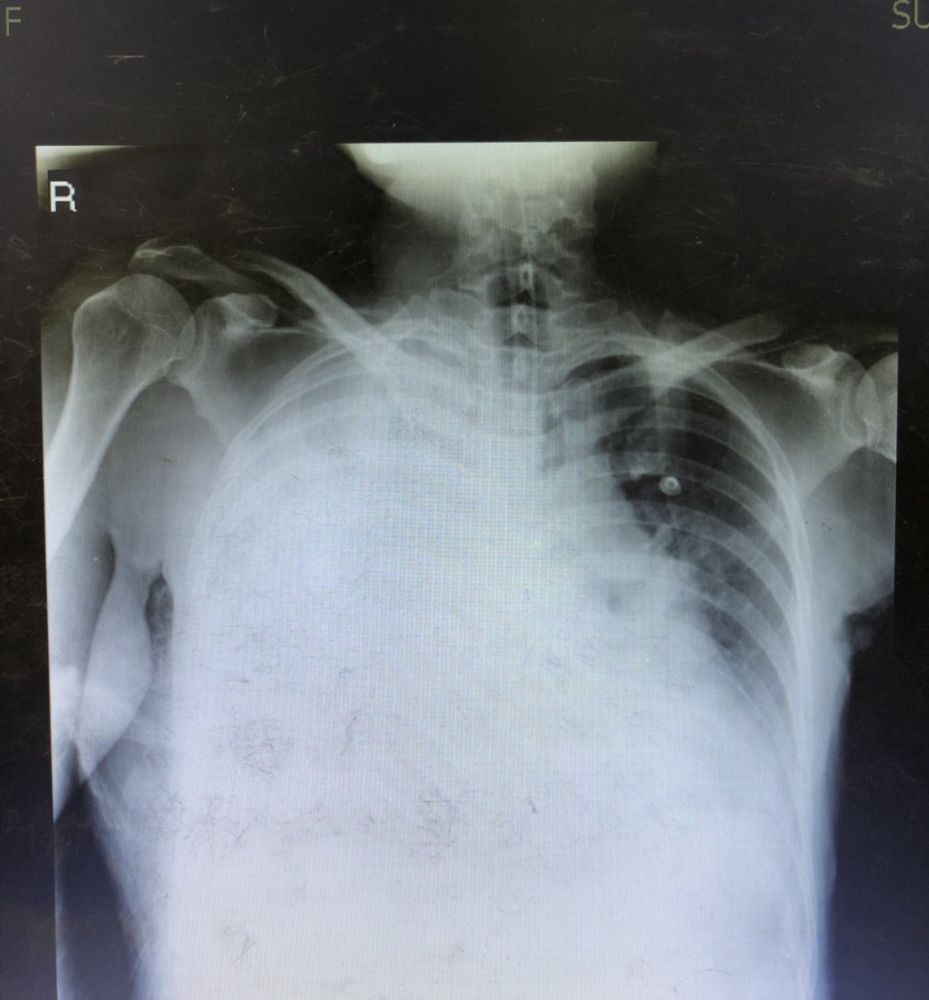

คุณจะรอดจากเวรICU วันนี้ไหม /ระดับบีกินนิ่ง

ICU เป็นแดนสนธยา สำหรับนักศึกษาแพทย์ ตอนเรียนไม่ค่อยได้มีบทบาท จบมาต้องดูแลเองเต็มๆ มาดูกันว่าคุณจะผ่านการอยู่เวร แบบแพทย์เวรรอด คนไข้ปลอดภัยไหม

1 จงบอกวิธีปรับventilator ที่เหมาะสม

2 คนไข้ septic shock เจาะblood gas ที่ oxygen canula 3LPMจงแปลผล

3 พยาบาลตามตีสอง คนไข้หอบ ทำไงคะเธอ

4 ตีสอง คนไข้หอบ แอร์ฮังเกอร์ what should i do?

5 เจาะน้ำตาลได้580ค่ะหมอ ส่งblood sugar cf แล้วค่ะ